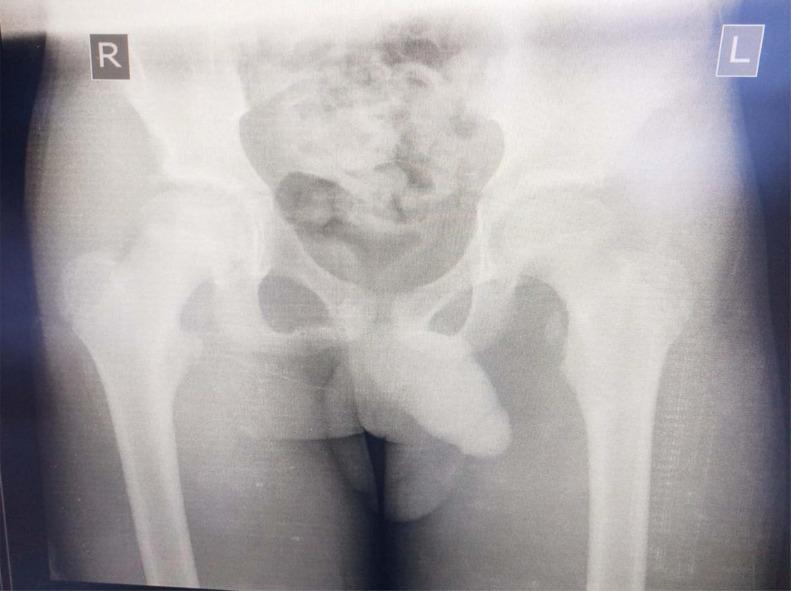

Avulsion of the lesser trochanter is a rare but disturbing condition, which usually occurs in males between the ages of 7-16 years with significant physical activities or in athletes. Diagnosis is more often than not challenging, but with a good history, physical examination, and imaging modality, diagnosis can be clinched, and the prognosis is good even with a conservative management approach. This case report is that of a 12-year-old male who suddenly fell while participating in sporting activities in school. As a consequence of the fall, he felt severe pain in the left groin region with an associated inability to bear weight on the affected limb. A radiograph study of the hip revealed a fracture of the left lesser trochanter. Based on the diagnosis, a conservative approach, which entails the use of analgesics, and partial weight-bearing mobilization with axillary crutches to take the weight off the affected limb for a period, was the choice of management for this subject. Fifteen weeks following the conservative management for the avulsion of the left femoral lesser trochanter fracture, the subject sustained a similar injury to the contralateral groin, consequential to return to sporting activities. In conclusion, rare as avulsion of the lesser trochanter may be, a high index of suspicion must be raised in any adolescent with a painful limp following engagement in any sporting activities, and such individuals should have a radiograph study done to achieve prompt and effective care.

摘要

小转子撕脱是一种罕见但令人困扰的病症,通常发生在7至16岁有大量体育活动的男性或运动员身上。诊断往往具有挑战性,但通过详细的病史、体格检查和影像学检查手段,可以确诊,即使采用保守治疗方法,预后也良好。本病例报告讲述的是一名12岁男性,他在学校参加体育活动时突然摔倒。摔倒后,他感到左腹股沟区域剧痛,且患侧肢体无法承重。髋部的X线检查显示左小转子骨折。基于该诊断,对于该患者,选择的治疗方法是保守治疗,包括使用镇痛药,并用腋拐进行部分负重活动,以使患侧肢体在一段时间内不负重。在对左股骨小转子撕脱骨折进行保守治疗15周后,该患者因恢复体育活动,对侧腹股沟遭受了类似损伤。总之,尽管小转子撕脱可能很罕见,但对于任何在参与体育活动后出现疼痛性跛行的青少年,都必须提高警惕,此类患者应进行X线检查,以便获得及时有效的治疗。